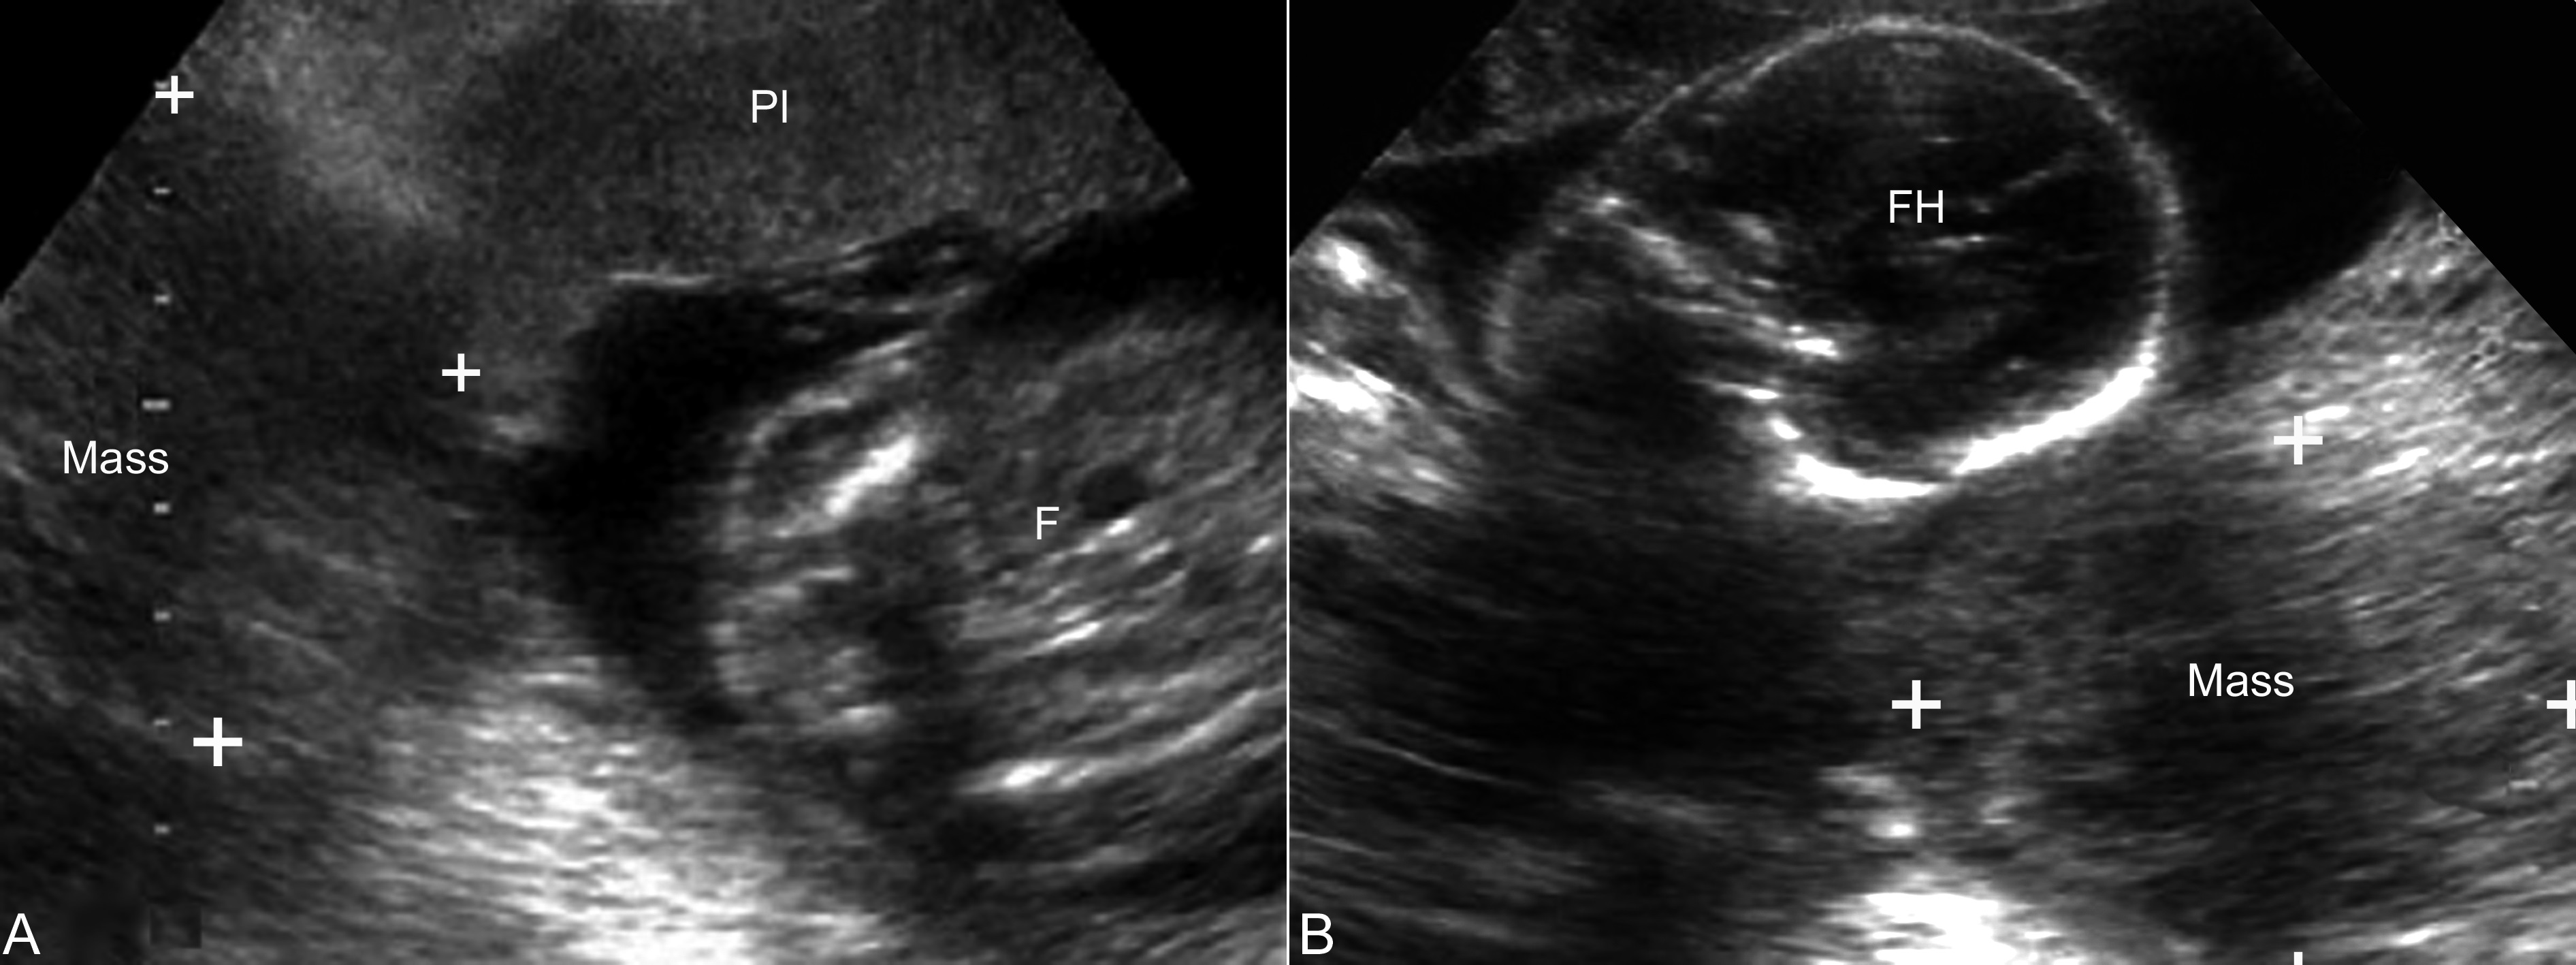

超声显像检查可在妊娠的各个时期发现,声像图表现为增大的子宫一侧或两侧、或于子宫后方局限性回声,肿瘤较小时显示形态规则,多数瘤体发现时已显示不规则,边缘不整齐、不清晰(图2),以原发病灶的性质不同内部回声的性质有所差异,多显示为较低的不均质回声,分布不均匀,CDFI检查内部可见点状或细小的血流显示,部分血流显示丰富(图3)。腹腔内多可显示不等的腹水。

图2库勃氏瘤声像图:妊娠子宫两侧均可显示实质性瘤体回声(Mass),Pl:胎盘;F:胎体;FH:胎头